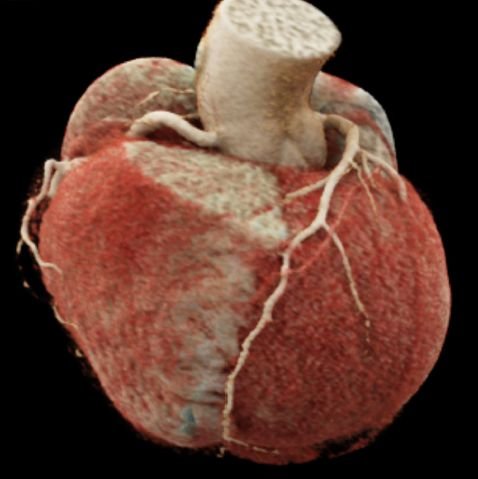

CT Cardiac Anatomy

CT Heart